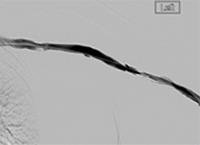

xray image of Iliac vein post-ZelanteDVT.

Iliac vein post-ZelanteDVT

xray image of liac vein post-PTA & stent.

Iliac vein post-PTA & stent

Femoral vein post-ZelanteDVT.

Femoral vein post-ZelanteDVT